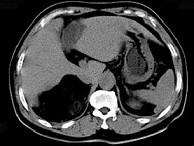

问题 男,59岁,右侧腰背酸痛,CT检查如图所示,应诊断为 ( )

选项 A、右腹膜后脂肪瘤 B、右肾血管平滑肌脂肪瘤 C、右肾上腺转移瘤 D、右肾上腺髓样脂肪瘤 E、右肾上腺腺瘤

答案 D